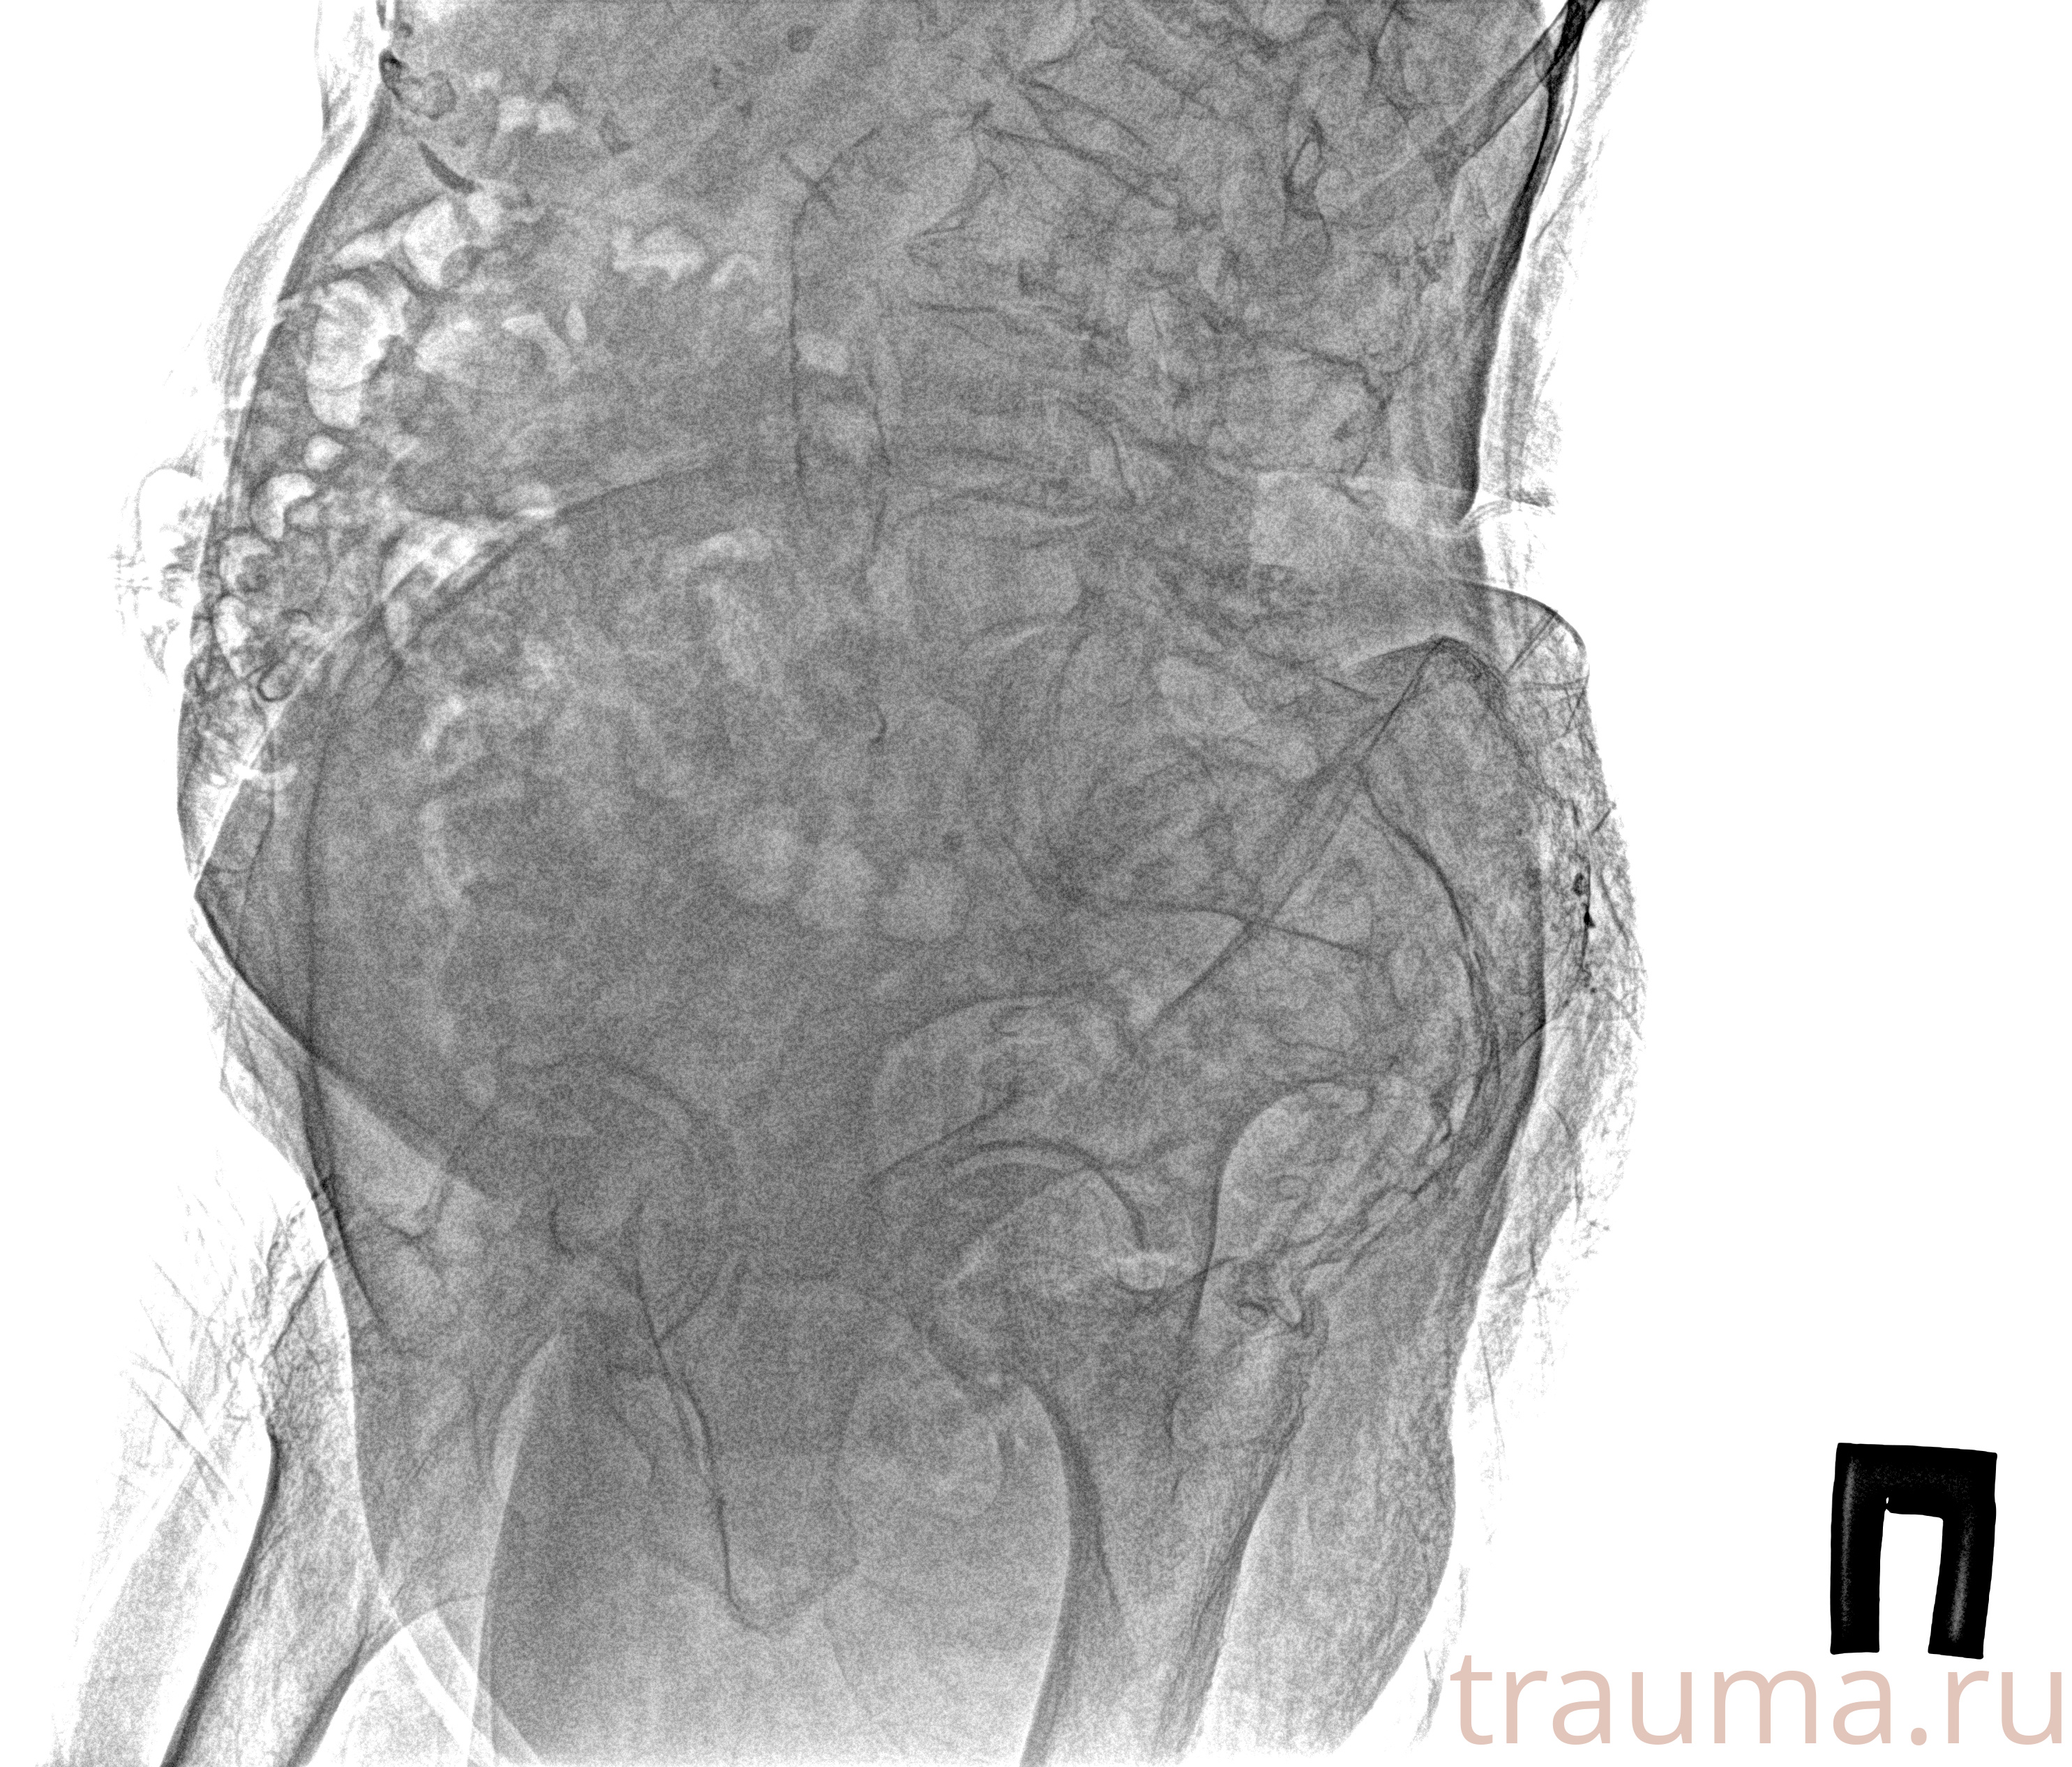

Рентген на дому: по вашему адресу приезжает врач-рентгенолог, травматолог-ортопед с мобильным рентгеновским аппаратом, проводит диагностику травмы или заболевания, делает необходимые рентгенограммы, дает рекомендации по дальнейшему лечению. Получить качественные снимки в домашних условиях возможно благодаря уникальной методике, разработанной МосРентген Центром для института  Склифосовского

Яркость: 1   Контраст: 1   Инвертировать: 0 Увеличение: 1

Перетаскивайте мышь вверх/вниз для контраста, влево/право для яркости. Прокрутка колесом изменяет масштаб. Нажмите Сбросить для возврата к исходному изображению. При увеличении держите мышь в той области, которую хотите рассмотреть.